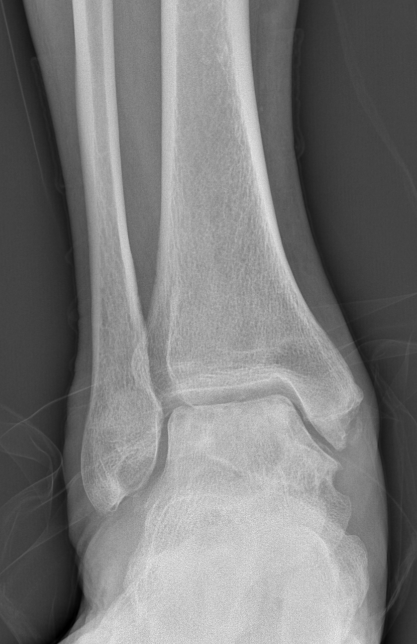

第一台手术的患者是位75岁的叔叔,被“脚脖子”痛缠了4年,疼得越来越厉害,病情已经到了严重阶段。

术前踝关节CT

术前后足力线X线

武勇主任团队给他做了3D打印导板辅助下人工全踝关节置换术。

这种手术适合踝关节病严重的患者,通过替换病变的关节结构,能帮着缓解疼痛、恢复关节活动,让老人日常走路更自在些。

术前踝关节侧位X线

术前踝关节正位X线